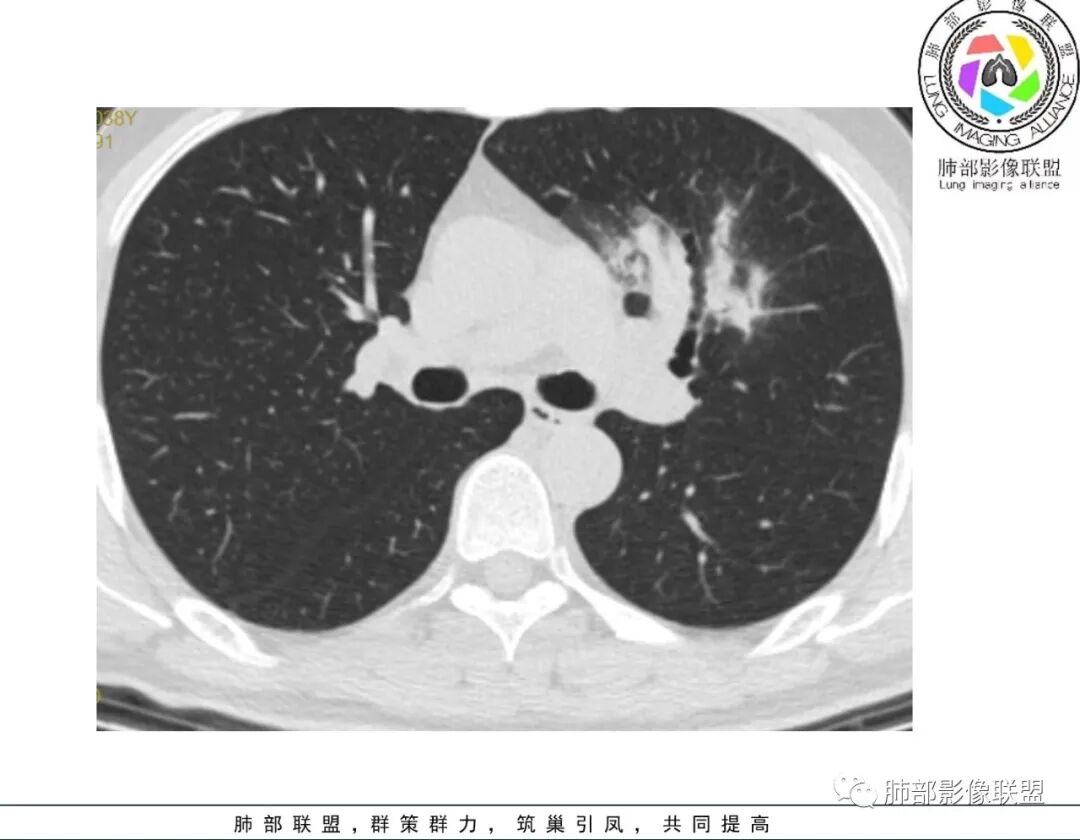

谢加平:左肺上叶和右肺下叶见多发散在性斑块病灶,边界清楚,部分见U形凹陷和刀切征,周围见模糊晕征,近胸膜下分布和蘑菇兄弟特点,累及左肺上叶上舌段支气管牵拉性扩张,前后13天复查整体病灶吸收不明显,有机化趋势表现,首选炎性肉芽肿(隐球菌感染?),请结合隐球菌荚膜抗原检查。

蓝天白云:两肺多发斑片状影,晕,内见扩张支气管影,可见直边,轻度延迟强化,纵隔肿大淋巴结,考虑炎性肉芽肿,隐球,淋巴瘤。

巴伟:双肺多发斑片影,边缘模糊,有晕,有支气管扩张,轻度强化,先考虑感染性病变,隐球,鉴别淋巴瘤。

穿越七海的风:双肺多发结节斑片影,边缘模糊有晕,亚急性病程,咳嗽黄痰,周围渗出,支气管张扩,胸膜增厚,复查病灶略有吸收,考虑感染性病变,隐球菌?

傅昌瑜:青年男性,咳嗽咳痰3周。白细胞计数稍升高,CRP正常。两肺多发斑片状、结节影,周围见边缘模糊磨玻璃影,部分边缘见毛刺,支气管穿行稍扩张。治疗后(具体药物不详),周围磨玻璃影减少,病灶似乎变小。无明显发热、白细胞无明显升高、CRP正常,治疗10天后复查吸收不明显,不支持细菌性肺炎。无发热、鼻窦疾病及血尿(未提供相关检查)等,血管炎可能性不大。肺内病灶形态单一类似、无树芽征,不支持肺结核。综合考虑隐球菌可能性大,鉴别淋巴瘤、血管炎。

2、影像资料:双肺多发的小结节、斑片状及不规则型的实性病灶,周围有晕,沿支气管血管束分布,部分的病灶周围可见磨玻璃样影、支气管的扩张以及小的空洞。增强扫描病灶,轻度强化内部见支气管造影征。部分的病灶,支气管有扩张,内壁凹凸不平的改变,纵隔淋巴结未见肿大。病灶整体的形态还是多样化,部分位于胸膜下。